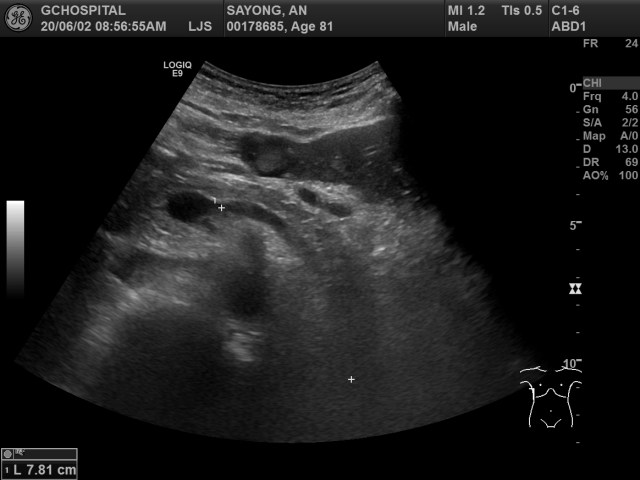

시행한 초음파영상에서 얻은 췌장의 횡단면 영상입니다.

췌장 꼬리에 위치해있던 종괴영상이 전혀 보이지 않았으며, 환자를 semi-upright position을 취하게 한 후 다시 확인해보아도 해당 종괴는 전혀 보이지 않습니다. 췌장의 목 부위에서 확인이 가능한 곳까지의 거리를 재보았더니 약 8센티미터정도가 나옵니다.

앞서 영상에서는 주파수가 4MHz였고, 포커스도 비교적 화면의 가운데 부분에 맞추어져 있었기 때문에, 좀 더 깊은 곳을 확인하기 위해 주파수를 3MHz로 낮추고 포커스도 최대한 깊은 곳을 볼 수 있게 맞추었습니다. 이렇게 해도 CT영상에서 보이던 췌장꼬리주변의 종괴는 전혀 보이지 않습니다.

즉, 이 환자는 탐촉자를 배 앞쪽에 대어서는 아무리 노력해도 췌장꼬리 부분을 확인하는게 불가능하다는 이야기입니다.